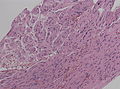

Microscopic

Features:[3]

• Perineural epithelioid cells.

• Abundant pale, fluffy appearing cytoplasm.

• Typical pseudo-onion bulbs.